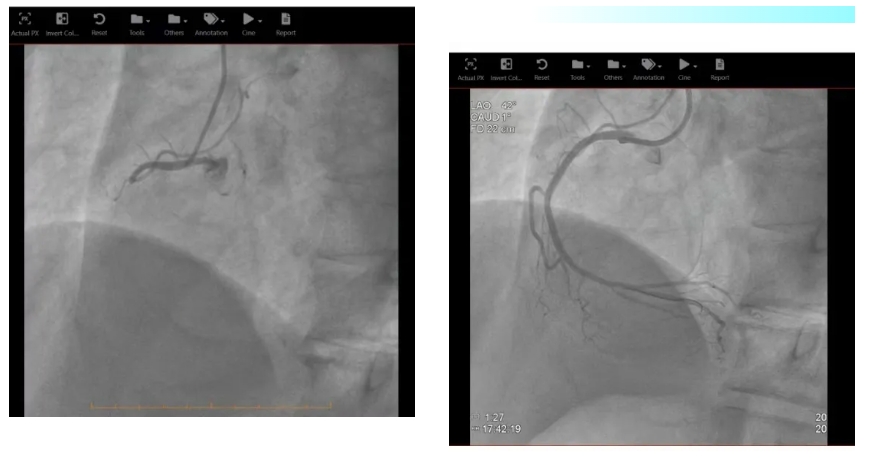

在完成必要的术前准备以及沟通后,由急诊科直接转运至心脏导管室,心内科刘茂月副主任医师主刀,医护团队凭借娴熟的技术,快速通过导丝、球囊扩张,成功于病变处精准植入两枚药物洗脱支架,血流瞬间恢复,患者的心脏得到了及时、有效的再灌注。手术过程顺利,术后患者生命体征逐渐趋于平稳。